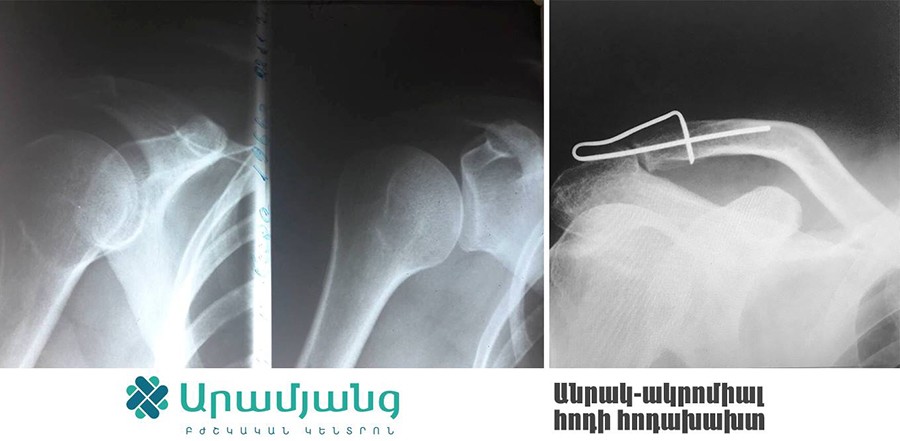

Արամյանց բժշկական կենտրոնի Օրթոպեդիայի ու Վնասվածքաբանության բաժանմունքում սկսել են իրականացնել բացառիկ վիրահատություններ հիշողություն ունեցող հատուկ մետաղի կիրառմամբ: Մետաղի օգտագործումն առավել արդյունավետ է դարձնում կոտրվածքների բուժումն ու պացիենտի արագ ապաքինումը:

Արամյանց Բժշկական կենտրոնի փոխտնօրեն, վնասվածքաբան-օրթոպեդ Միքայել Բուռնուչյանի խոսքով՝ սառեցնելով 0-5 աստիճան՝ այս մետաղը հնարավոր է ծալել ու կիրառել ցանկացած դիրքով՝ կախված կոտրվածքի տեղակայումից: Հետո այն մարմնի ջերմության ազդեցությամբ 37-40 աստիճանում կվերադառնա իր նախնական  դիրքին՝ ապահովելով ոսկրաբեկորների կոպրեսիան:

Մետաղն իր արդյունավետությամբ կարող է փոխարինել նմանատիպ վիրահատությունների ժամանակ կիրառվող մետաղալարին և պտուտակին: Այն իր մեջ պարունակում է ուժ, որն էլ հենց ոսկրաբեկորները պահում է մշտական կոմպրեսիայի վիճակում. արդյունքում ոսկրացման ընթացքն ավելի է արագ է տեղի ունենում: Այն որոշ դեպքում կարելի է կիրառել անգամ Իլիզարովի ծանր ու խոշոր ապարատի փոխարեն՝ազատելով պացիենտին լուրջ անհարմարությունից:

Ընդ որում, մետաղը տեղադրելու համար պետք է ընդամենը քիչ ինվազիվ և փոքր միջամտություն կատարել: Մետաղը առաձգական է և ամուր, այն նիկելի և տիտանի խառնուրդ է, ունի տարբեր չափսեր ու ձևեր, որոնք կիրառվում են ըստ դեպքի ու ցուցումի: